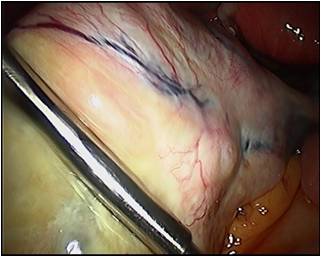

Total Laparoscopic Hysterectomy (TLH) is the best way to remove a diseased uterus. It can also be done by the vaginal route (NDVH) . Unfortunately not all hysterectomies can be performed vaginally whereas almost all can be done Laparoscopically.

Benign ovarian cysts including dermoids are removed in this way. Almost all ectopic pregnancies are operated laparoscopically. Fibroids (benign tumours of the uterus) are best removed laparoscopically . As expected the results are far superior to those of open surgery both in the short term al well as longterm.

Endometriosis is best treated by Laparoscopic excision.

Yes. Total Laparoscopic Hysterectomy (TLH) with pelvic lymphadenectomy (removal of lymph glands from the pelvic region) is well established as treatment of low-risk Endometrial cancer. Laparoscopic Radical Hysterectomy is now well established treatment for early Cervical cancer. Many cases of Ovarian cancers can also benefit from laparoscopic approach (esp. to judge operabilty and to stage inadequately operated cases).

We are actively promoting Laparoscopic Oncological surgery in suitable cases and Laparoscopic Pelvic lymphadenectomies are undertaken on a regular basis.